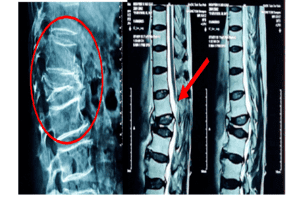

Hình ảnh X-quang và MRI: biến chứng chèn ép tuỷ do gãy L1 điều trị không đúng cách

(Nguồn: Khoa Ngoại thần kinh – BVĐK Trà Vinh)